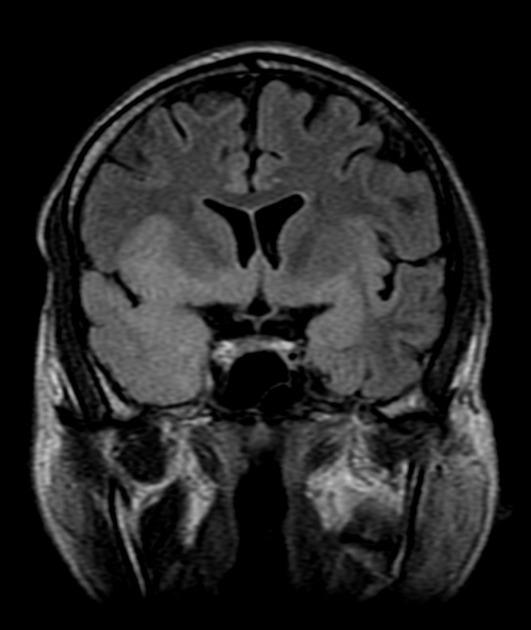

Рисунок 1 | Асимметричные области патологически повышенного МР сигнала в медиальных отделах обеих височных долей, больше выраженные в корковом веществе

Рисунок 2 | В последовательности DWI у того же пациента определяются области повышения сигнала в обоих лобно-височных областях. ИДК подтвердила ограничение диффузии

Т1-взвешенное корональное изображение после введения контраста демонстрирует асимметричное двустороннее гириформное и лептоменингальное контрастное усиление больше в области коры островка (большие стрелки) и поясной извилины (меньшая стрелка)